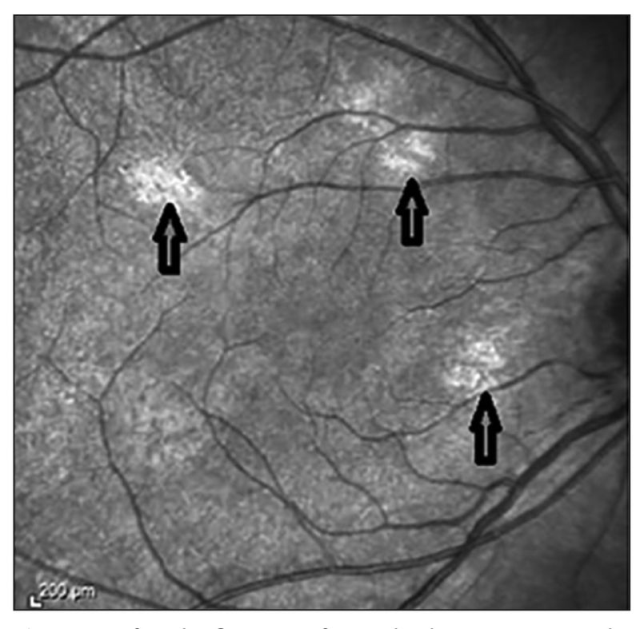

Çalışma kapsamında 19 hastanın gözleri incelenmiştir. Araştırma ekibi, optik koherens tomografi (OCT) adı verilen ileri bir görüntüleme yöntemi sayesinde gözün arka kısmında yer alan koroid tabakasında NF1'e özgü bulguların kolay ve ayrıntılı biçimde görüntülenebildiğini ortaya koymuştur.

Dr. Sakarya ve ekibinin bu çalışması yalnızca tanı sürecini kolaylaştırmakla kalmamış, hastalığın izlenmesi açısından da yeni bir dönemin kapısını aralamıştır. Elde edilen sonuçlar, oftalmoloji alanında dünyanın en prestijli dergileri arasında yer alan American Journal of Ophthalmology, Investigative Ophthalmology & Visual Science, British Journal of Ophthalmology ve Acta Ophthalmologica'da yayımlanan çalışmalarla doğrulanmış ve bu yayınlara atıf yapılmıştır. Ayrıca American Journal of Ophthalmology'de yayımlanan bir tez çalışmasında ve Springer Yayınevi tarafından basılan "Pediatrik Sistemik Hastalıklarda Göz" adlı kitapta da bu araştırmaya yer verilmiştir.

Bilim dünyasında geniş yankı uyandıran bu çalışmaların ardından, 2021 yılında güncellenen Nörofibromatozis tip 1 tanı kriterleri Genetics in Medicine dergisinde yayımlanmıştır. Güncellenen kriterlere OCT ile saptanabilen koroid bulguları da dahil edilmiştir. Bunun yanı sıra Almanya'da yayımlanan Nörofibromatozis tip 1 tanı rehberinde de Dr. Yaşar Sakarya ve arkadaşlarının çalışmasına atıf yapılmıştır.